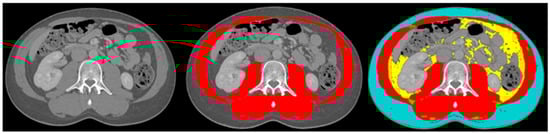

The body composition analysis was performed by two trained researchers (DC and SJ) according to previously published protocols [19,23]. A single slice of the CT scan at the lumbar level L3 was used, as this corresponds with total body muscle and fat mass [24,25]. Slice-O-Matic software (5.0 Rev-8, Tomovision, Milletta, QC, Canada) was used. Relevant tissues were identified based on their anatomical features and tagged with a colour as explained in Figure 1. The software multiplies preset Hounsefield units (HU) with pixels for the tagged area to calculate the relevant areas. The areas of interest, the thresholds and the definitions used are summarised in Table 1. Sarcopenia was present if the skeletal muscle area (SMA) corrected for height2 was below reference values. For myosteatosis as a surrogate marker for muscle quality, the muscle attenuation in Hounsefield units was used; myosteatosis was considered to be present if it was below the reference value. The subcutaneous, visceral and intermuscular adipose tissue areas were added up to calculate the total adipose tissue area. If this area was below the reference value, adipopenia was present.

Figure 1.

Example body composition analyses. Left image: cross-sectional image at lumbar level L3; middle image: tagged muscle mass (red colour); right image: tagged subcutaneous adipose tissue (blue colour), visceral adipose tissue (yellow colour), intermuscular adipose tissue (green colour) and muscle mass (red colour).